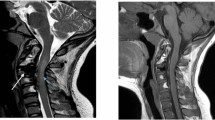

We present the case of an 84-year-old man who suffered an observed cardiopulmonary arrest. Cardiopulmonary resuscitation was initiated and spontaneous circulation returned. In the emergency room, the patient’s Glasgow Coma Scale was 3 (E1V1M1). No spontaneous respiration was noted. Neuroimaging revealed SAH at the CVJ. Contrast-enhanced computed tomography (CT) revealed a vessel running through the left C2/3 intervertebral foramen into the spinal canal. The ventral space of spinal cord revealed contrast enhancement. Angiography revealed extravasation from the spinal branch of the left vertebral artery, without venous filling. It did not appear to be a vascular malformation with an arteriovenous shunt, but rather a traumatic laceration of the artery. Plain CT and CT angiography suggested AAD. Magnetic resonance imaging revealed injury to the medulla oblongata and upper cervical spinal cord, with AAD and retrodental subligamentous hemorrhage. We embolized the branch of the left vertebral artery and performed a C1 laminectomy. The patient moved his extremities postoperatively.